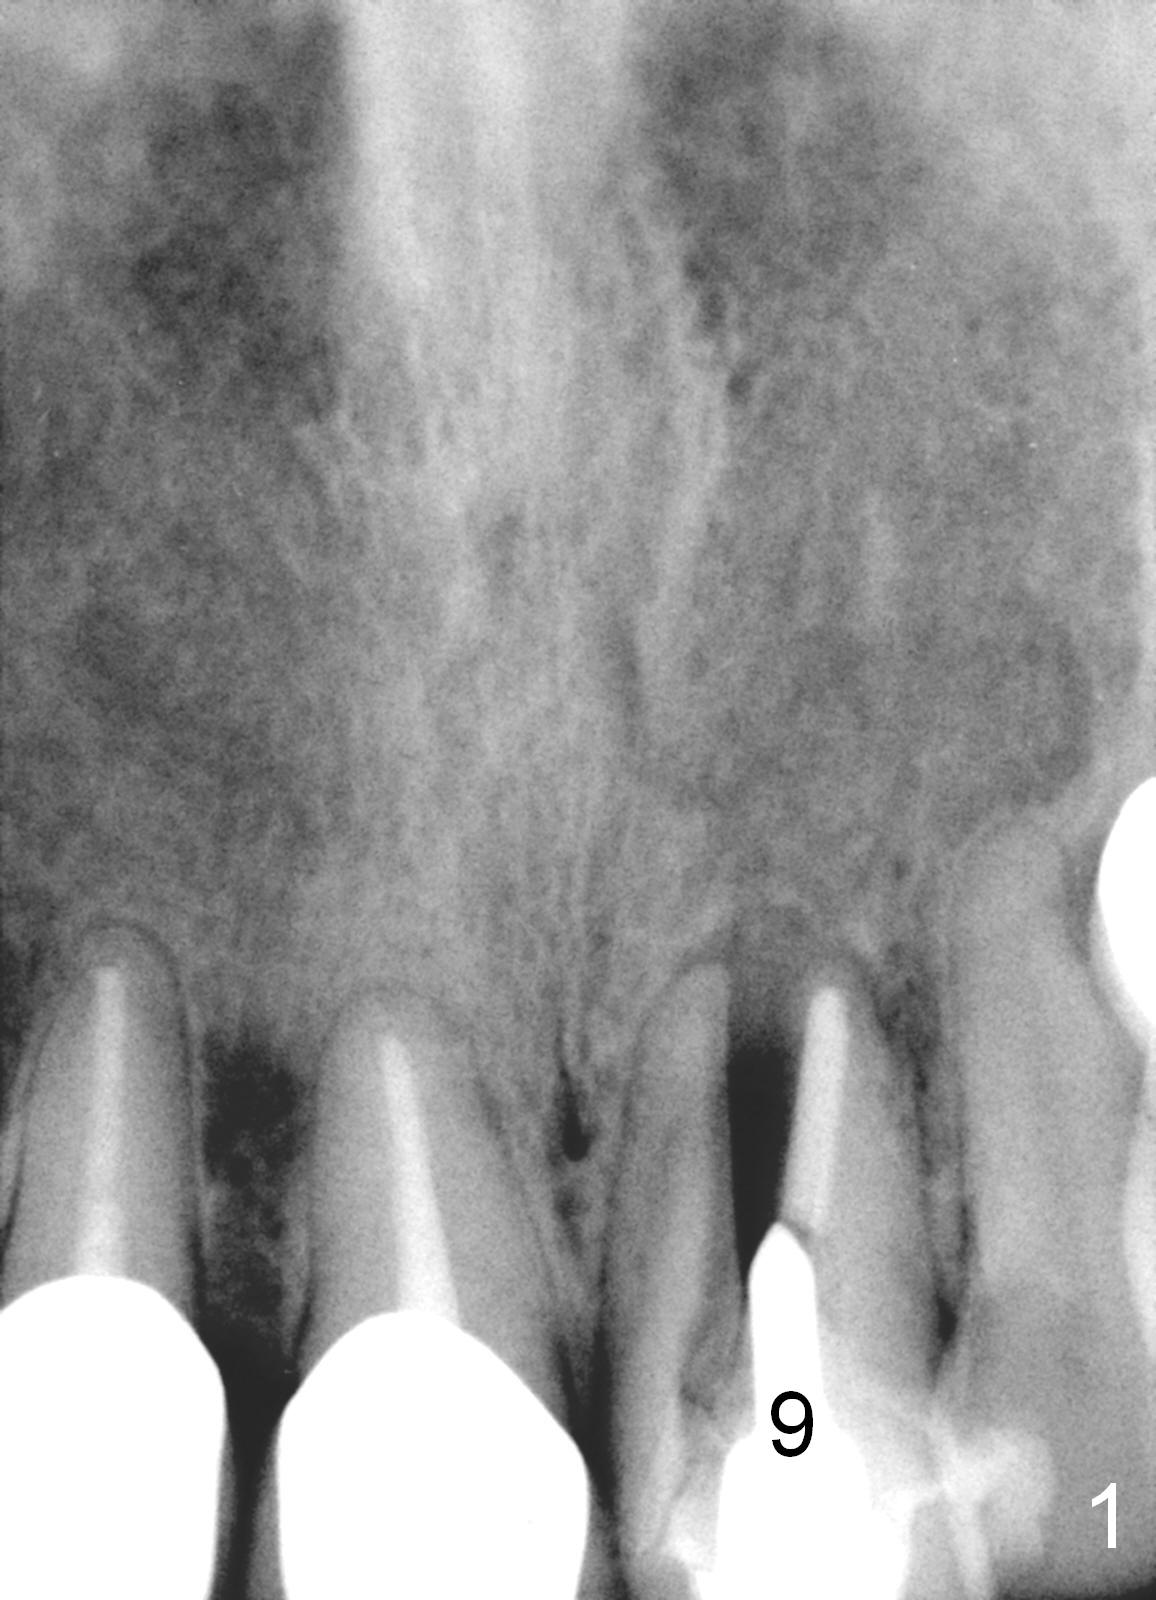

A 64-year-old woman (XP) has multiple restoration, requesting implant replacement for the loose upper left central incisor (Fig.1). It is asymptomatic, although there is labial swelling with purulent discharge from the labial gingival sulcus. The labial plate must have been absent. After granulation tissue removal and socket treatment with no antibiotic, place a 4x16 mm implant in a correct position (Fig.2). Place Osteogen tape against the labial defect and then bone graft with a small piece of gauze in the implant well. Since the lady is small in stature with possible osteoporosis and X-ray is particularly dark (Fig.2 (Fig.1 has been lightened in brightness)), use low voltage when taking new X-ray. Take preop photos to show labial swelling and purulent discharge from the labial gingival sulcus.